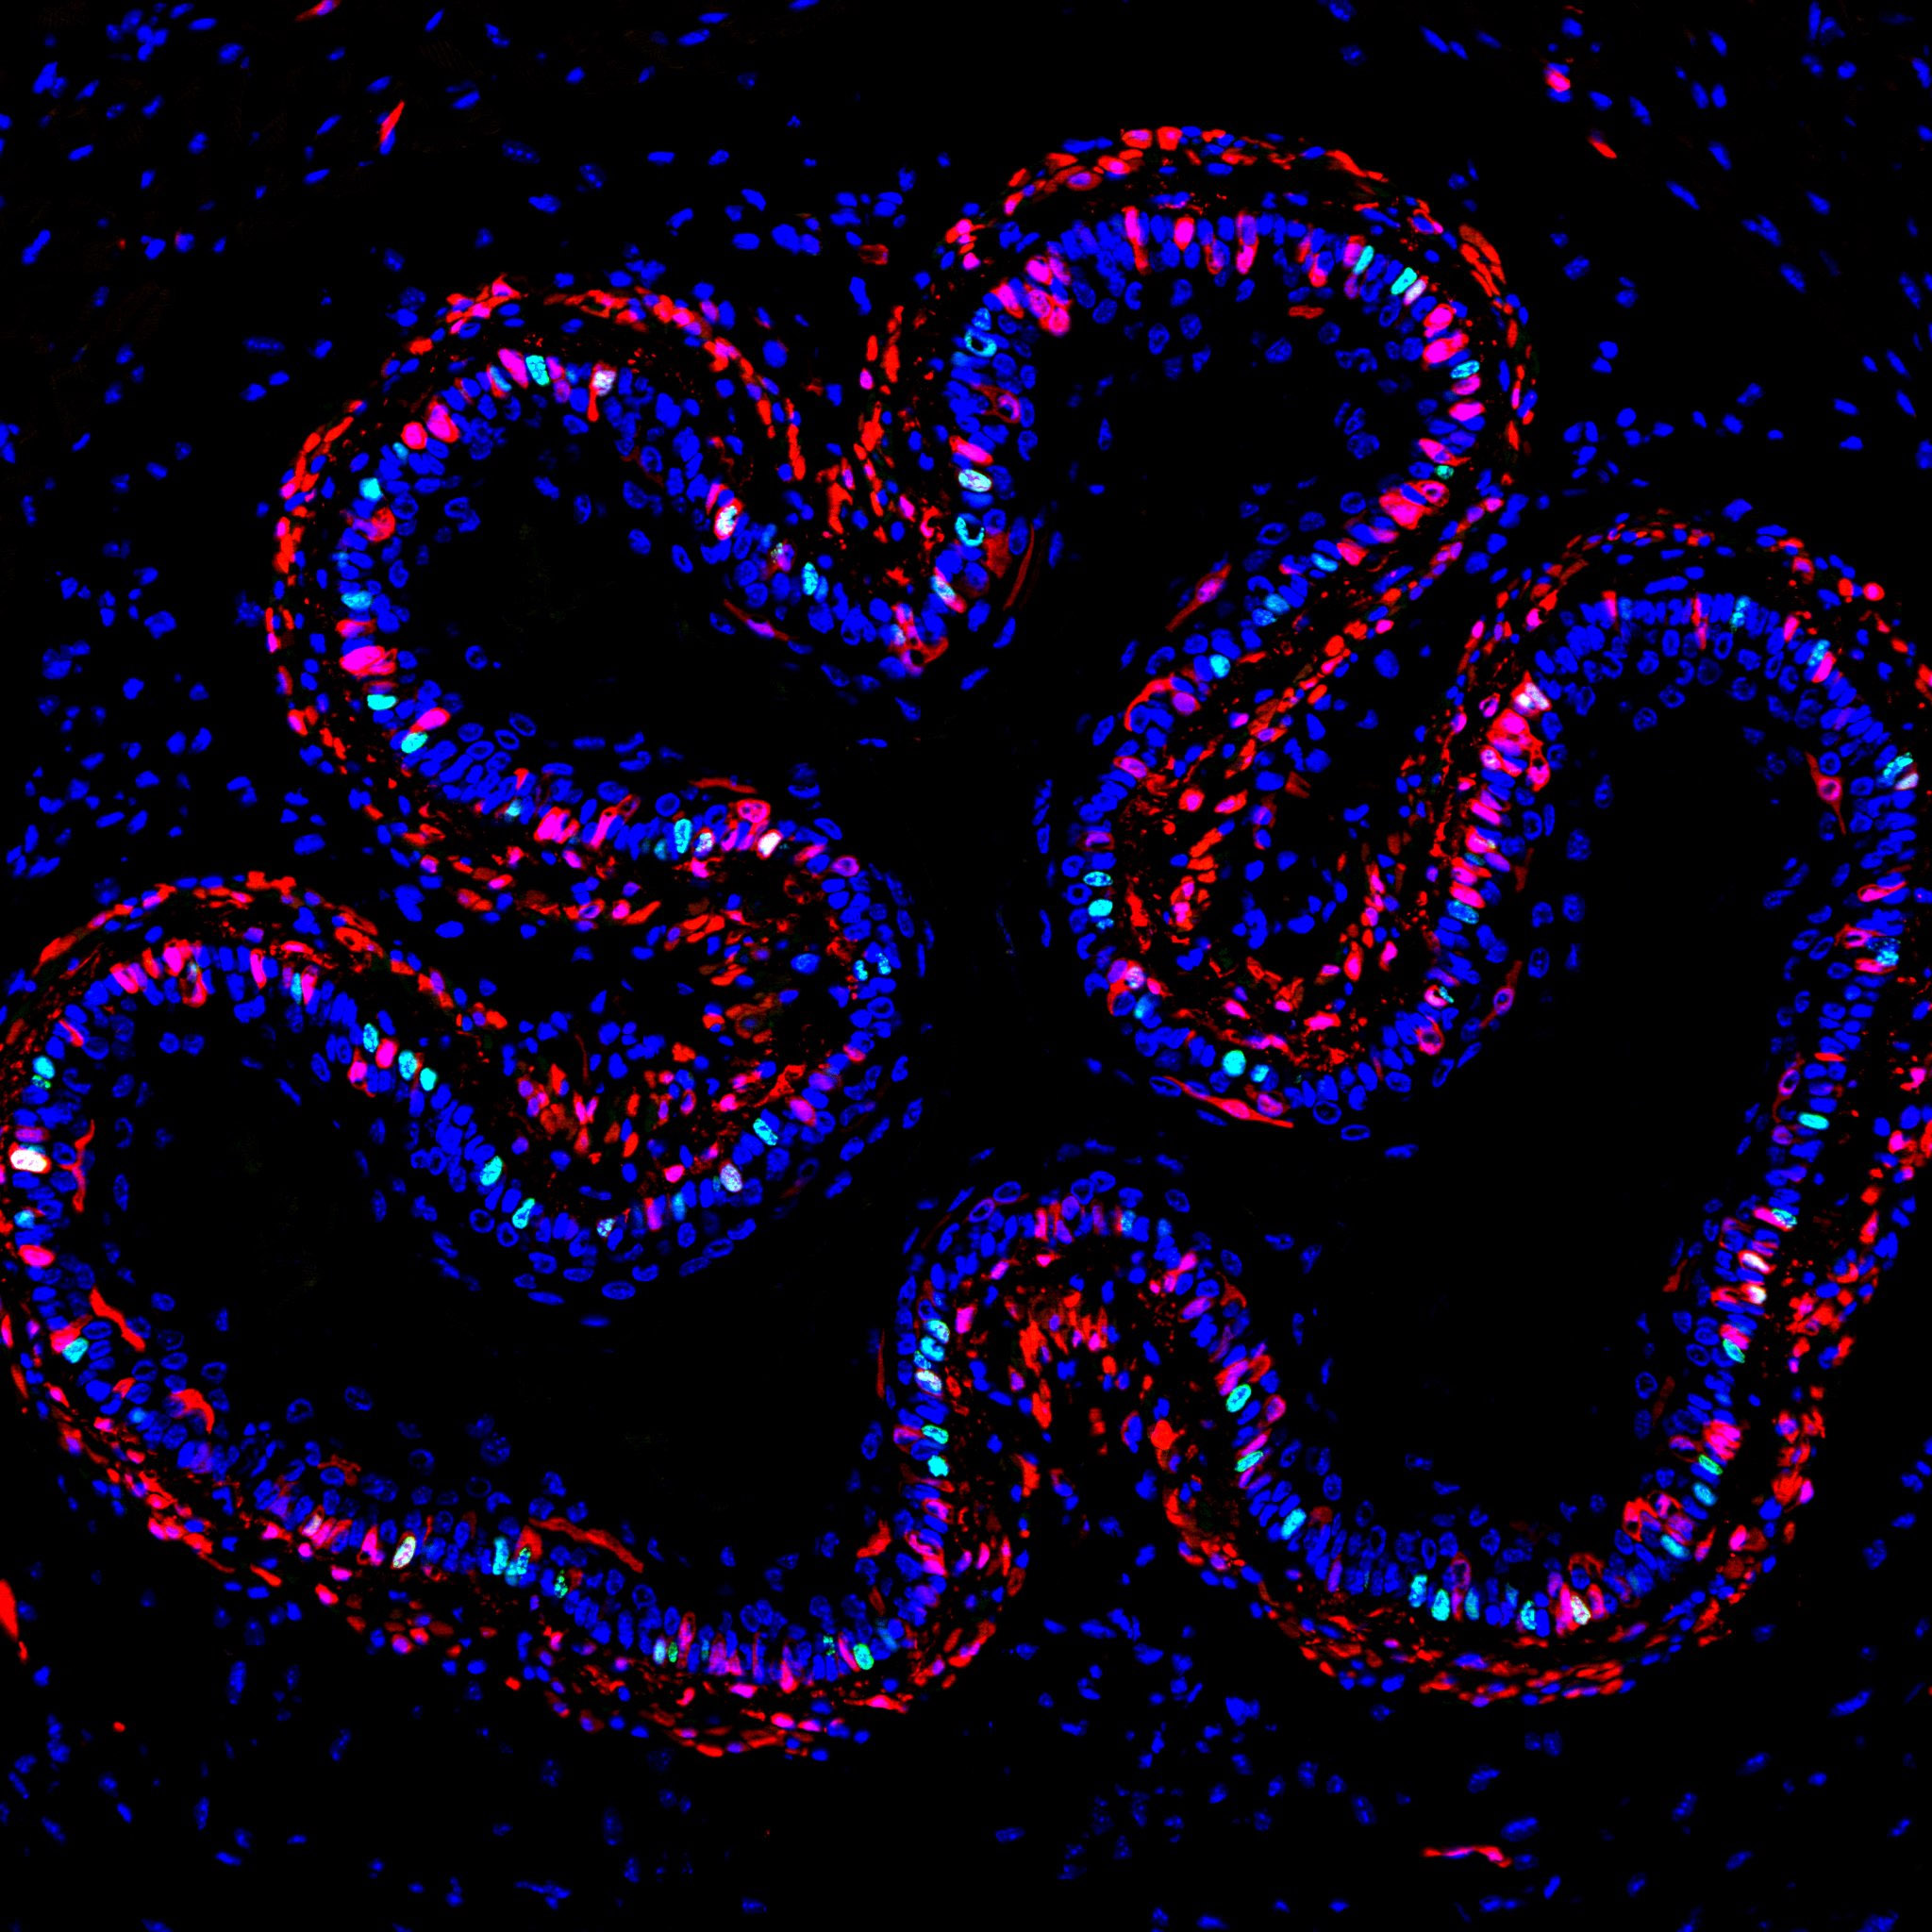

Cross section of the oesophagus, delineating Troy+ progenitors and fibroblasts in red.